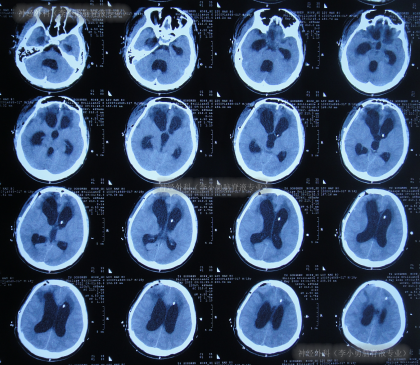

去骨瓣减压术后43天即2022年3月16日,查头颅CT示仍严重脑积水(图-7)。

图-7:2022年3月16日头颅CT

因脑积水进一步加重,于2022年3月28日(去骨瓣减压术后55天),进行了脑室腹腔分流术。术后次日查头颅CT示脑室分流术后有出血(图-8)。

图-8:2022年3月29日头颅CT